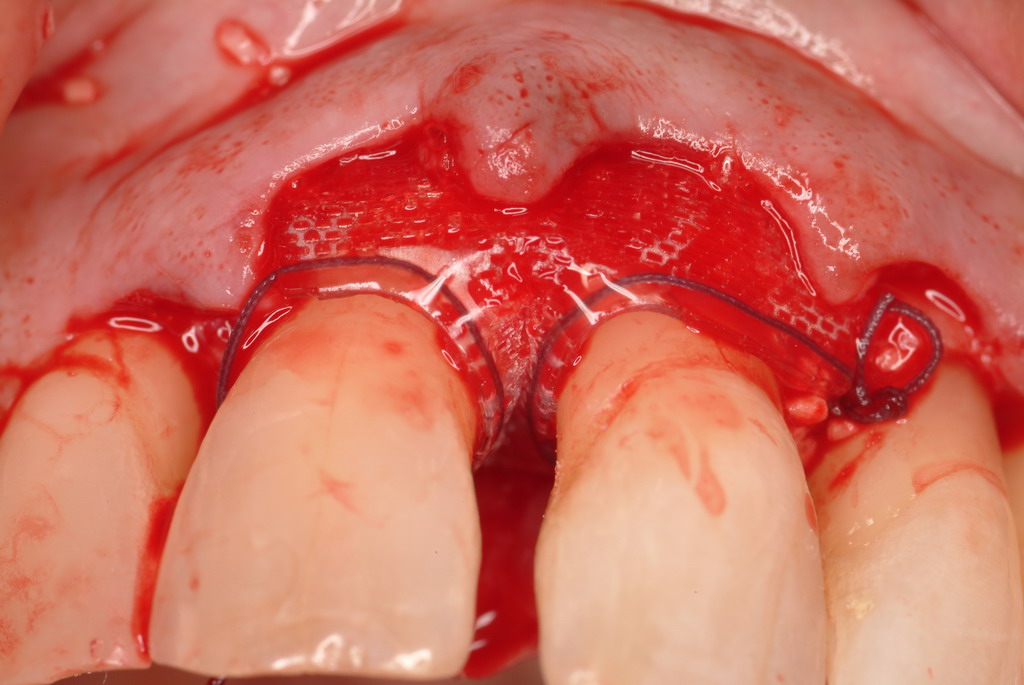

A resorbable membrane sutured around the teeth bordering the intrabony defect.

Figure 15